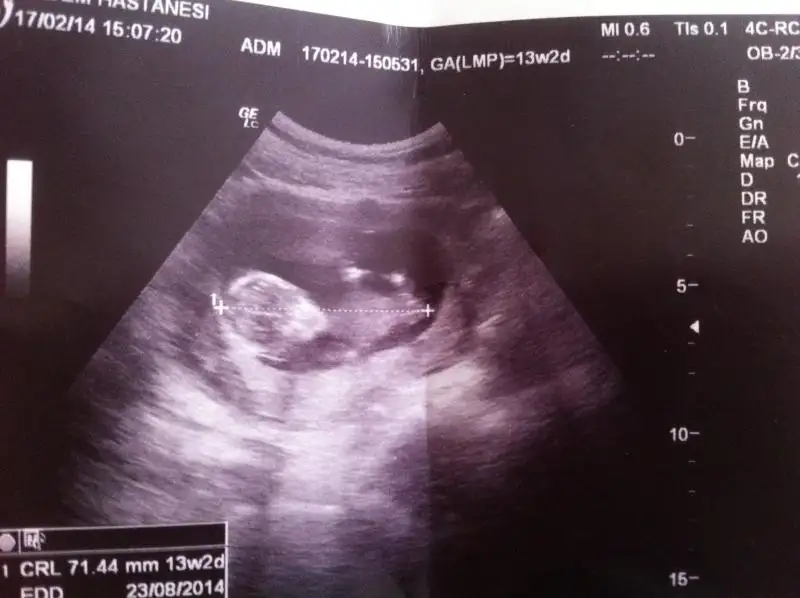

dr soylemeden siz gorun genital nub teorisi ( bebegin cinsiyeti)

$IMG_2633.webp merhaba kızlar 13+3 haftalık cinsiyeti çok merak konusu:44: evimizde ilk bebeğimiz allah biliyor ya gönlüm hep kızdan yana sağlıklı sihatli olsun en öncelik o tabi takipteyim lütfenn benimkinde ne görünüyor dr söylemedi :50:

Kiza benziyo canim ama nubu net goremedn soyluyorum bi ihtimal